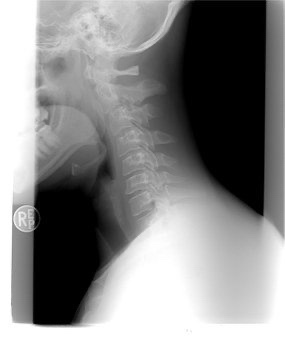

연하검사란 보통 비디오 투시 연하검사를 많이 하시는데요.

비디오 투시 연하검사

VFSS , video fluoroscopoc swallowing test

비디오 투시 연하검사는 조영제를 섞은 다양한 점도의 음식들을

차례로 섭취하는 모습을 x-ray 검사 시 사용하는 x-선을 사용하여 보고

이를 비디오로 녹화하는 방식입니다.

물, 미음, 죽, 밥 등의 다양한 점도의 음식을 섭취하게 합니다.